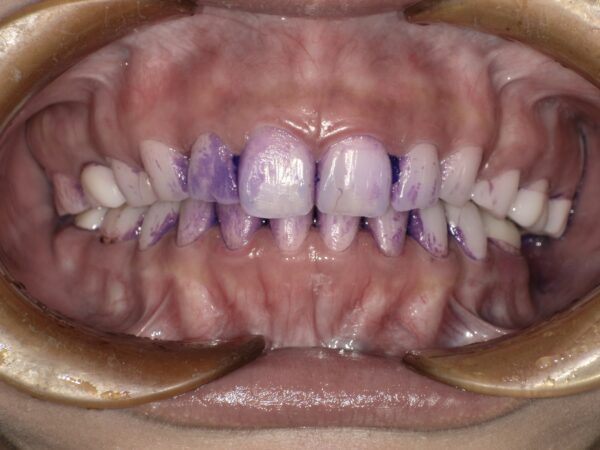

当院でメンテナンスをされている方はご存知かと思いますが、当院ではクリーニングの前にプラーク(歯垢)の染め出しを行っています。

染め出しの主な目的は、プラークを視覚的に確認することです。

プラークは、歯の表面に残る細菌の塊で、これが放置されると虫歯や歯周病の原因になってしまいます😭

しかし、プラークは歯と同じ色をしているので肉眼ではっきりと見ることができないため、染め出し液を使ってプラークがどこにどのくらい残っているかを目で見て確認できるようにするのです💡

それを元に歯ブラシの当て方やどんな補助用具を使えば効率的に磨けるかなどを歯科衛生士がアドバイスさせていただいています。

また染め出しをすることで、私たち歯科衛生士もプラークが残っているところを重点的に確認しながらクリーニングを行うことができるため、取り残す確率も減らせるうえに必要以上にクリーニングし過ぎてしまう事もなくなり、まさに一石二鳥‼️